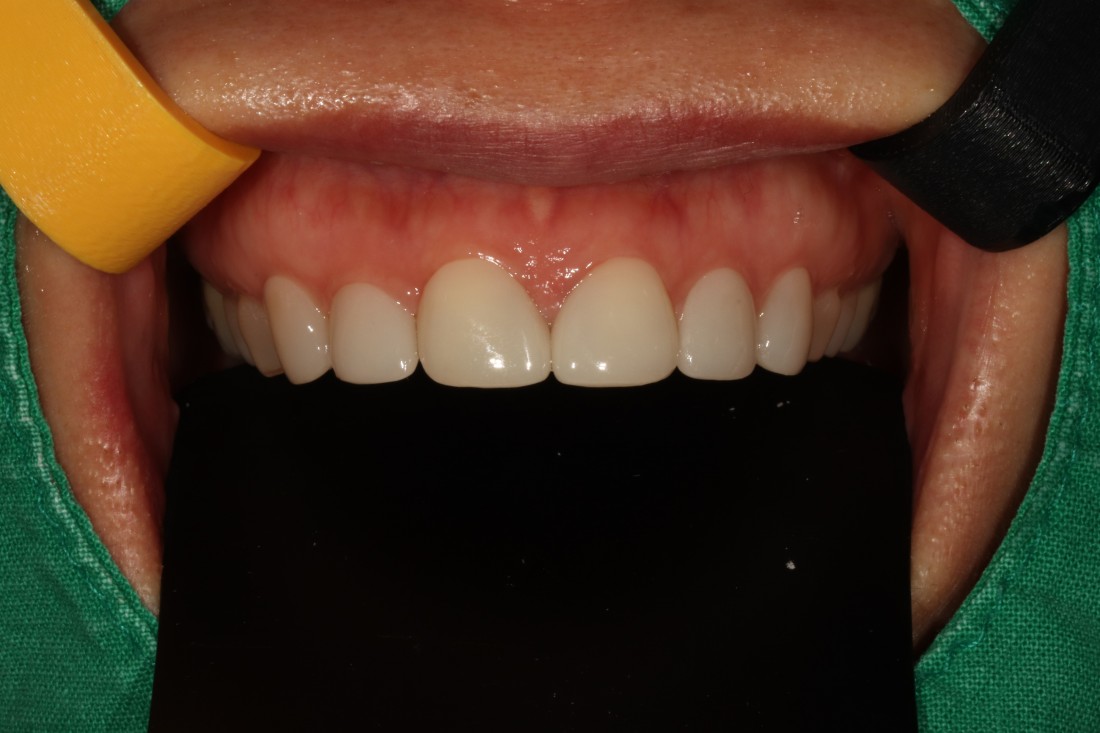

그렇지만 실제로 라미네이트 전/후 사례를

200케이스 가까이 공유하는

라미네이트 치과를 찾기는

쉽지 않은데요.

광주 무삭제 라미네이트 치과는

벌어진 앞니 / 깨진 앞니 /

얼룩덜룩한 앞니 / 왜소치 등

다양한 사례의 라미네이트 전-후 사진을

투명하게 공개하고 있습니다.